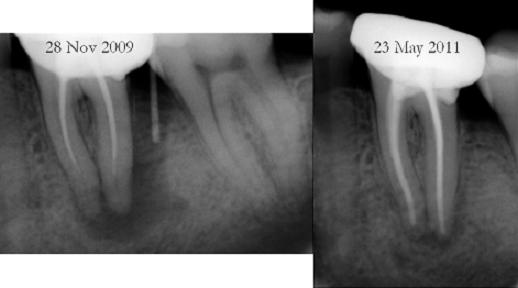

See the pics below of a successful retreatment, fig 3 is pre and fig 4 is post treatment

Successful retreatment requires elimination of bacteria which is achieved by cleaning canals to correct apical sizes, when done correctly it can be very rewarding for the dentist and patient, see the bone formation leading to almost complete healing, pic below- Continue to READ MORE